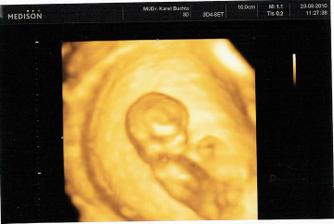

23.8.2010 první UTZ v ČR. Byli jsme zrovna 11tt+5 ale mrňousek odpovídal velikosti 12tt+1. NT Sreening dopadnul dobře a my jsme dostali první fotečky.